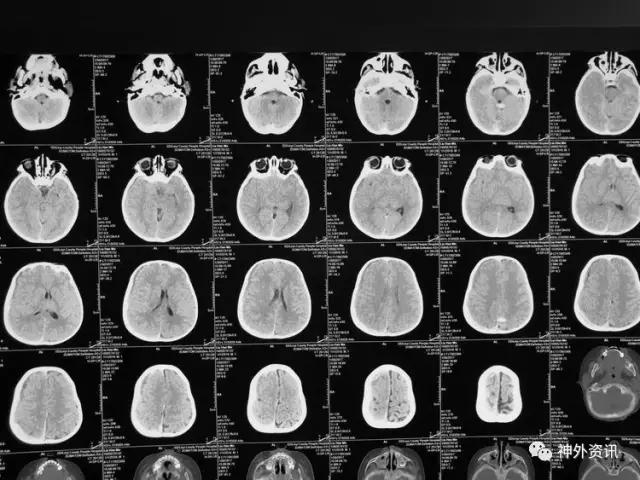

患儿刘**,男,19个月,2017.1.30 2pm不慎摔倒,意识障碍,刺痛不睁眼,不发音,刺痛肢体屈曲,急至当地医院,伤后1小时颅脑CT结果示右额颞顶枕急性硬膜下血肿,中线轻微左移:

3小时后转至我院急诊科,当时查体:刺痛不睁眼,不发音,刺痛右侧肢体屈曲,右侧瞳孔5mm,对光反应消失,左侧瞳孔0.3cm,对光反应迟钝,立即术前准备并复查CT,结果示右额颞顶枕硬膜下血肿,右侧大脑半球及左侧额叶弥漫性低密度,考虑缺血,中线左移明显,脑沟及环池显示不清:

术后移动CT结果示中线移位较术前减轻,顶枕部蛛网膜下腔出血:

2017.2.1:术后2天复查颅脑CT,结果示中线居中,右侧半球低密度并SAH,左侧半球未见明显异常,左侧脑沟可见显示,双肺少量炎症,不能放松警惕,继续同前治疗。

2017.2.4:术后5天复查颅脑CT,结果示中线居中,左侧半球及环池显示清晰,右侧半球脑沟显示欠清晰,脑组织低密度较前有所好转,继续同前治疗。已加用预消化肠内营养液及促进胃肠动力药物。

2017.2.6:术后7天,复查颅脑CT示情况较前进一步好转,逐步撤掉冰毯,缓慢自然复温。

2017.2.8:术后9天,复查颅脑及胸部CT,结果显示双侧脑沟脑回及环池显示清晰。颅压控制,拔除引流管探头,头部敷料稍加压包扎,此时已更替力月西为丙泊酚,停用呼吸机。